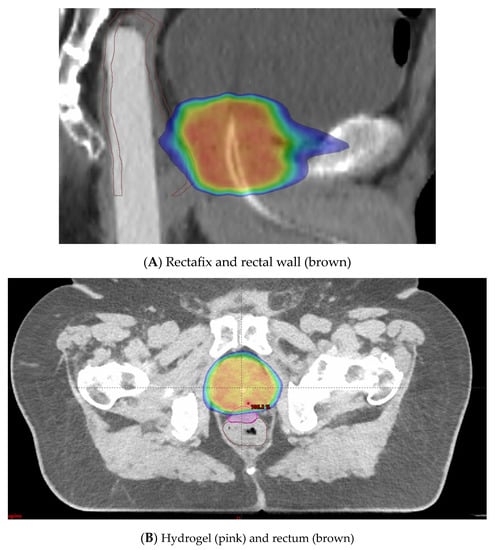

A rectal displacement device is a rigid device that aims to reduce variations in rectal filling and intrafraction movement. It works by pulling the posterior rectal wall away from the prostate and thereby decreasing the radiation dose to the rectum (Figure 5A) [14,71].

Figure 5.

(A) Rectafix in use to mitigate circumferential rectal radiotherapy doses. (B) Hydrogel in use to prevent high radiotherapy doses to anterior rectal wall. Blue is 50% isodose distribution. Red is 100% isodose distribution.

Hydrogel spacer placement is an alternative method employed to minimize rectal toxicity. The anterior rectal wall lies in close proximity to the prostate, with only 2 to 3 mm typically separating the target volume from this dose-limiting OAR [72]. Injection of a hydrogel spacer to increase this distance can be employed (Figure 5B). This allows the higher radiation doses to fall in the spacer region instead of the anterior rectal wall. A systematic review and meta-analysis on perirectal hydrogel spacer placement with 1011 patients [73] showed that this method was associated with less rectal irradiation, fewer GI toxicities, and higher bowel-related quality of life in the long-term follow-up. This study also showed with 486 patients that the space between the rectum and prostate had a median distance of 11.2 mm. In a multicentre trial, 222 patients were randomized to hydrogel injection and no injection [74]. The trial demonstrated a decrease in rectal dose and a significant reduction in late rectal toxicity (2.0% versus 7.0% in the control group, p = 0.04) with the use of hydrogel insertion.